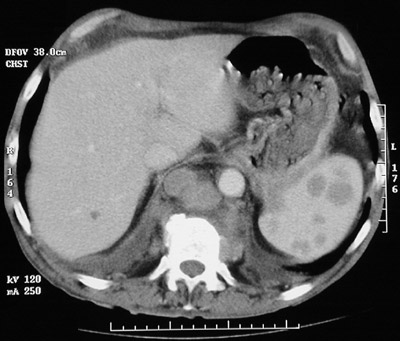

![]() | This abdominal CT scan reveals a larger and several smaller splenic mass lesions representing extranodal involvement by Hodgkin's disease. There is also prominent lymphadenopathy. In the view below from another patient, more prominent splenic involvement by Hodgkin's disease is seen. |